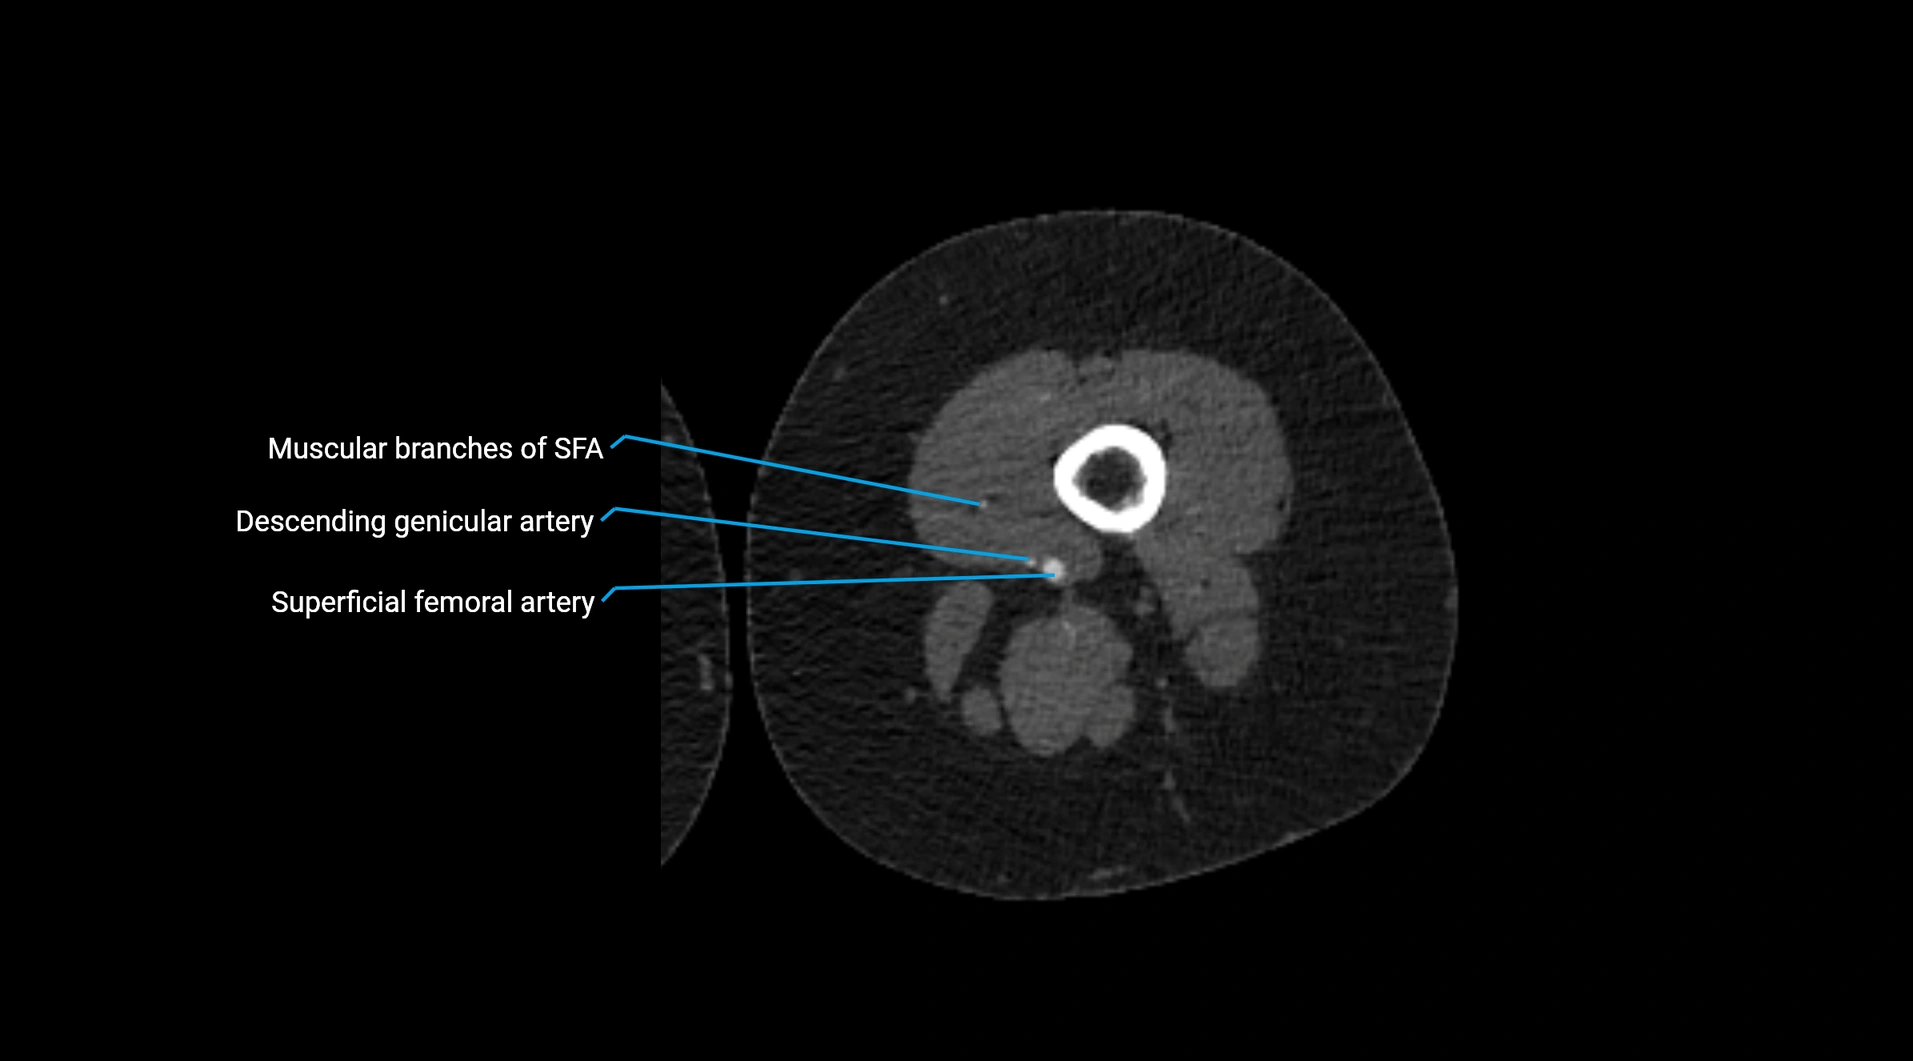

CT Appearance

Non-contrast CT:

• Appears as a tubular soft tissue structure anterior to vertebral bodies

• Calcified atherosclerotic plaques appear as hyperdense foci along the wall

• Useful for screening abdominal aortic aneurysm (AAA) size and mural calcification

Contrast-enhanced CT (CTA):

• Gold standard for abdominal aortic imaging

• Provides excellent detail of lumen, wall, aneurysm, thrombus, and branch vessels

• Multiplanar and 3D reconstructions help in aneurysm measurement, stent graft planning, and dissection evaluation

• Detects acute rupture, traumatic injury, or occlusion with high sensitivity

CT images

image